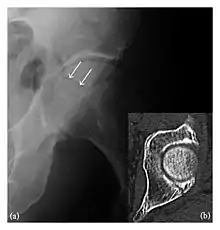

High-energy trauma fractures

Occult osseous injuries may result from a direct blow to the bone by compressive forces of adjacent bones against one another or by traction forces during an avulsion injury. Lesions in the tibial plateau, hip, ankle, and wrist are often missed. In a tibial plateau fracture, any disruption of the posterior and anterior cortical rims of the plateau should be sought. Impaction of subchondral bone will appear as an increased sclerosis of the subchondral bone (Figure 1). In the hip, posterior acetabular fractures also present subtle radiographic findings. The acetabular lines should then be carefully examined keeping in mind that the posterior rim, which is harder to see on X-rays, is more frequently fractured than the anterior rim (Figure 2). In the wrist, detection of carpal bone fractures is often challenging, with up to 18% of scaphoid fractures radiographically occult. Carpal fractures, especially the scaphoid, are associated with the risk of avascular necrosis. In apparently normal wrist radiographs from symptomatic patients, if there is history of a fall on an outstretched hand with pain in the anatomic snuffbox, suggesting scaphoid injury, the initial examination with posteroanterior, lateral, and pronation oblique views must be complemented by other specific views such as supination oblique and the "scaphoid" view A careful examination of cortices for evidence of discontinuity or offset and cancellous bone for lucency is necessary (Figure 3).[1]

Figure 3: A 26-year-old man presenting with wrist pain after being assaulted. (a) Initial anteroposterior radiograph shows a subtle linear lucency within the scaphoid extending to the scaphocapitate articular surface that was overlooked (arrow). (b) Initial "scaphoid" view was negative. (c) Followup anteroposterior radiographs, 12 days later, shows obvious scaphoid fracture (arrows).[1]

Figure 4: Dorsal triquetral fracture of the left wrist in a 30-year-old man after a trauma. (a) Anteroposterior radiograph shows a normal appearance. (b) Lateral radiograph of the same wrist demonstrates a chip fracture off the dorsal aspect of the triquetrum (arrow).[1]